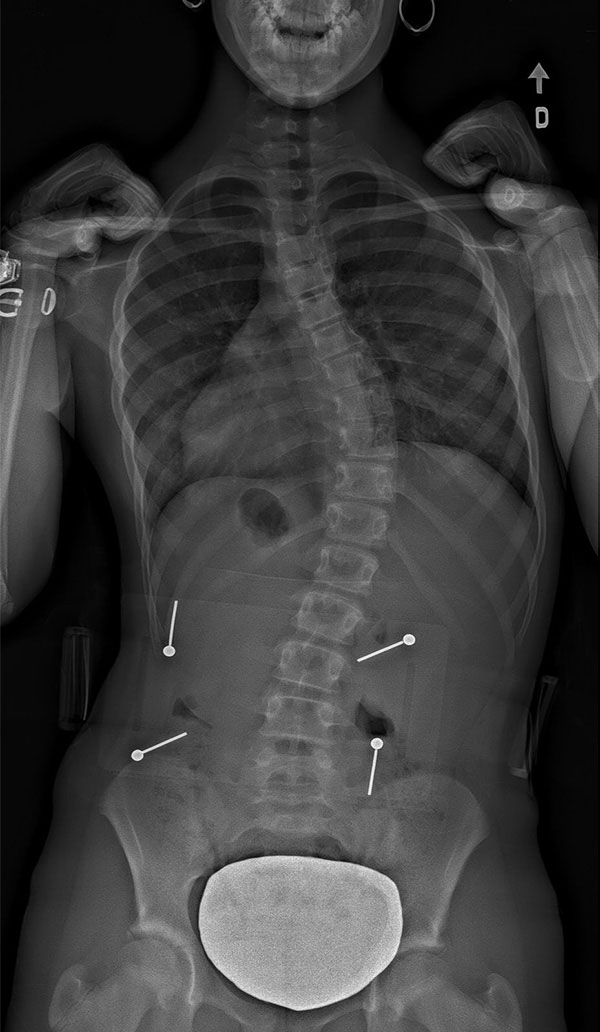

Scoliose thoracique (dorsale) – située dans la région de la colonne vertébrale où se trouvent les côtes.

![]() |